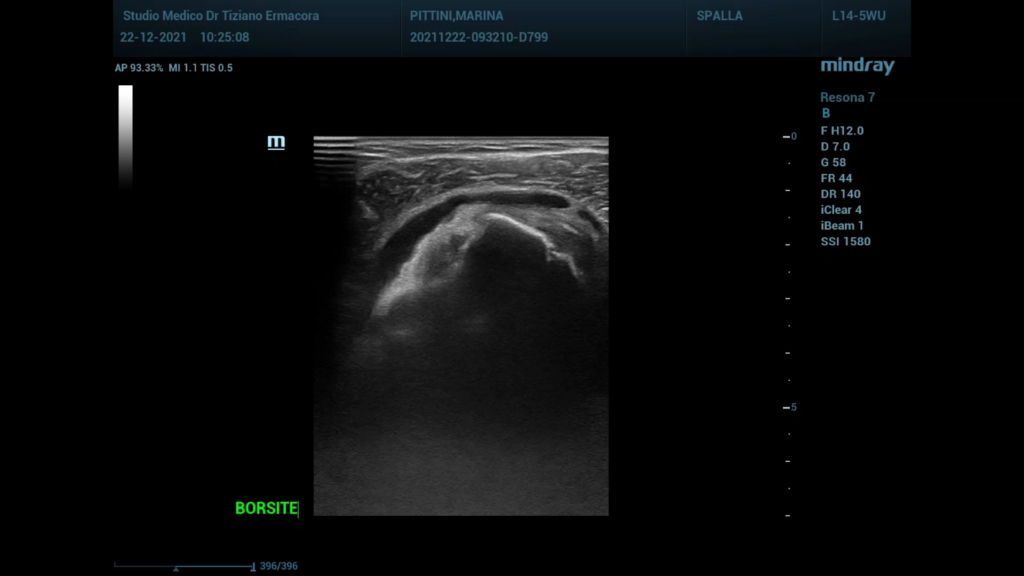

Lesione della cuffia dei rotatori

Paziente con dolore alla spalla dx,all’es.ecografico versamento nella borsa subacromialee lesione del tendine sovraspinato ben…